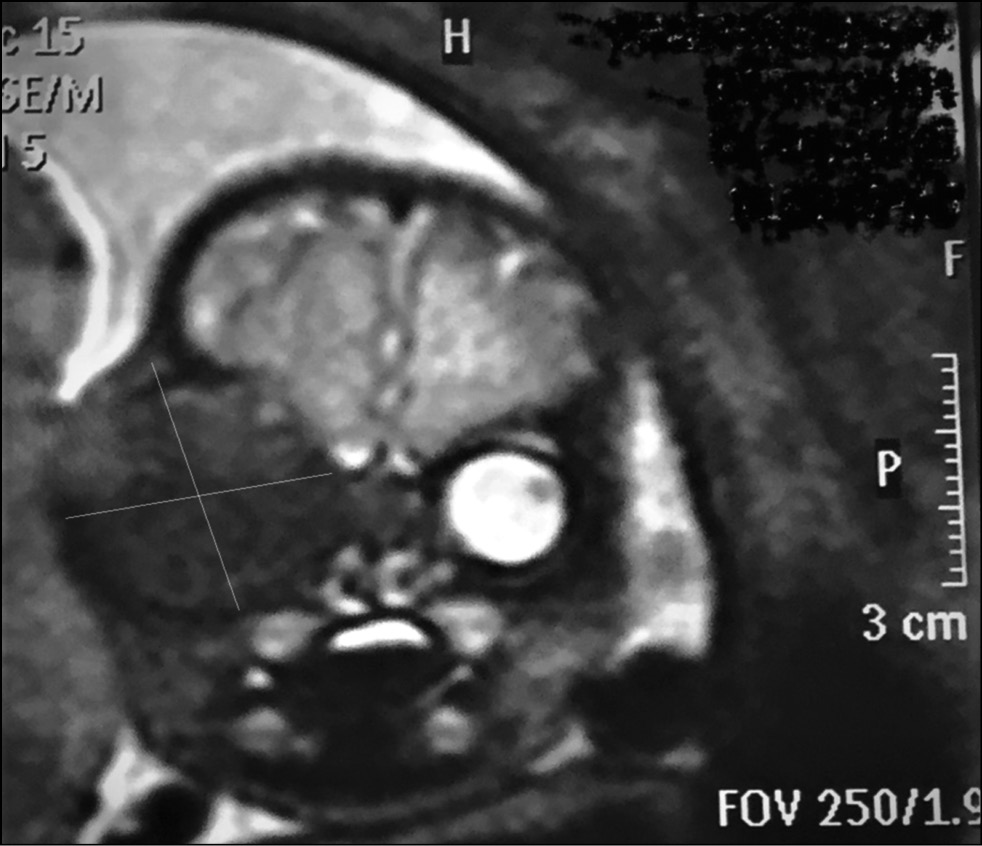

Клинический случай 3. Пациент Ш. 30 лет. Беременность вторая. Первая беременность закончилась рождением доношенного ребёнка, в настоящее время возраст 5 лет, здоровый. Наследственность по РБ не отягощена. На учёте в женской консультации с 12 недель беременности. Прошла плановое УЗ-скрининговое обследование в 1-м и 2-м триместрах, врождённой патологии плода не выявлено. Результаты пренатального эхографического обследования в 3-м триместре (ГВ плода — 31 неделя) были следующими: правая орбита плода увеличена (диаметр 33 мм) за счёт эхогенного образования неоднородной структуры округлой формы. Глазное яблоко диаметром 16 мм, смещено кпереди, хрусталик без особенностей. Левая орбита и содержимое без патологии. Заключение: образование правой орбиты плода (ретинобластома?). Рекомендовано МРТ плода, которое было проведено через 5 дней (рис. 5) и 14 дней. На серии изображений МРТ головного мозга и прицельно орбиты плода в динамике установлено быстрое интракраниальное распространение опухоли вдоль канала зрительного нерва; значительное увеличение экзофтальма, что позволило с высокой степенью вероятности предположить злокачественный характер патологии. Перинатальный междисциплинарный консилиум (врач лучевой диагностики, неонатолог, нейрохирург, офтальмолог) с участием будущих родителей рекомендовал прерывание беременности по медицинским показаниям. Последующий гистологический анализ опухоли подтвердил диагноз внутриутробной РБ.

Рис. 5. Изображении МРТ: образование правой орбиты плода (ретинобластома?).

Fig. 5. MRI image: formation of the right orbit of the fetus (retinoblastoma?).

Третий клинический случай указывает на быстрый рост и интракраниальное распространение опухоли при внутриутробном её происхождении.